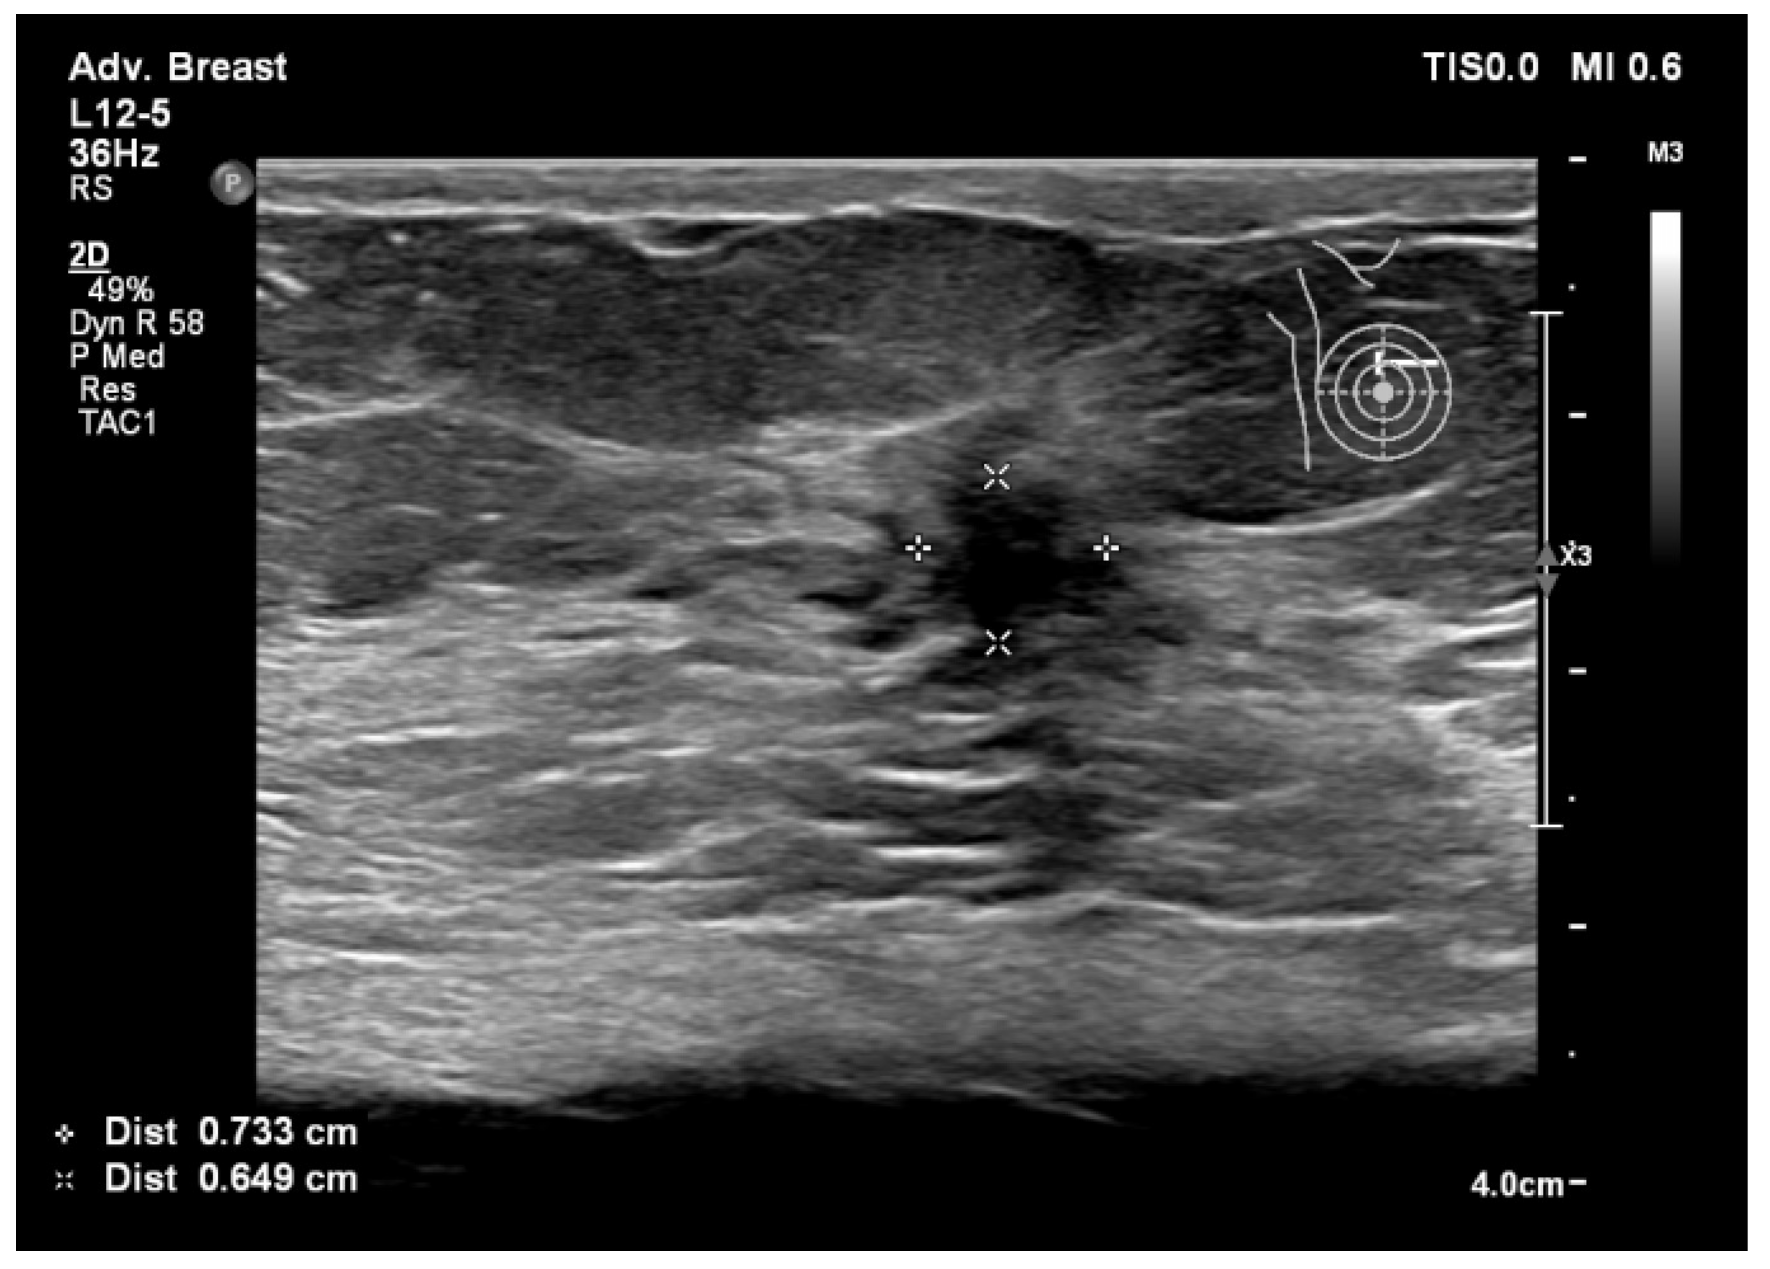

6.1. Characterization of Lesions

6.2. Real-Time Imaging and Guided Biopsies